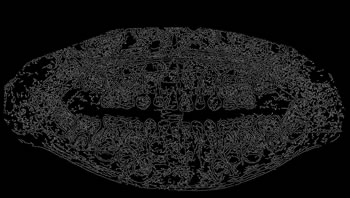

To thoroughly benchmark the methods studied here, the 1,500 images were distributed among 10 categories. The images were named, using whole numbers, in sequential order by category, aiming at not identifying the patients in the study. The process of categorizing the images was performed manually, selecting images individually, counting tooth by tooth, as well as verifying structural characteristics of the teeth. The images were classified according to the variety of structural characteristics of the teeth (see Table 5). Finally, the images were cut out to disregard non-relevant information (white border around the images and part of the spine) generated by the orthopantomograph device. After the clipping process, there was a change in the size of the images to 1991 ×\times 1127 pixels, but without affecting the objects of interest (teeth), as shown in Figure 2. The cropped images were saved on the new dimension to be used in the following stages, which will be presented in the next sections. Figure 3 shows an X-ray image corresponding to each of the categories of our data set.

Refer to caption

Figure 3: Examples of images from the data set categories of present work: (a) Category 1; (b) Category 2; (c) Category 3; (d) Category 4; (e) Category 5; (f) Category 6; (g) Category 7; (h) Category 8; (i) Category 9; (j) Category 10.